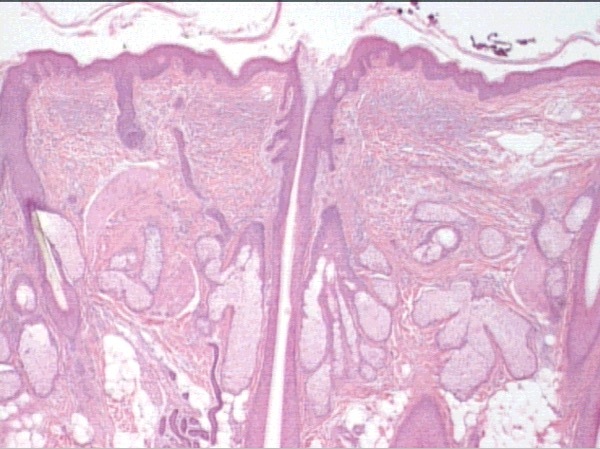

epidermis - SSE keratinized

dermis - dense irregular CT

stratum basale

stratum spinosum

stratum granulosum

stratum lucidum

stratum corneum

epidermis

thin skin, no lucidum

papillary dermis

reticular dermis